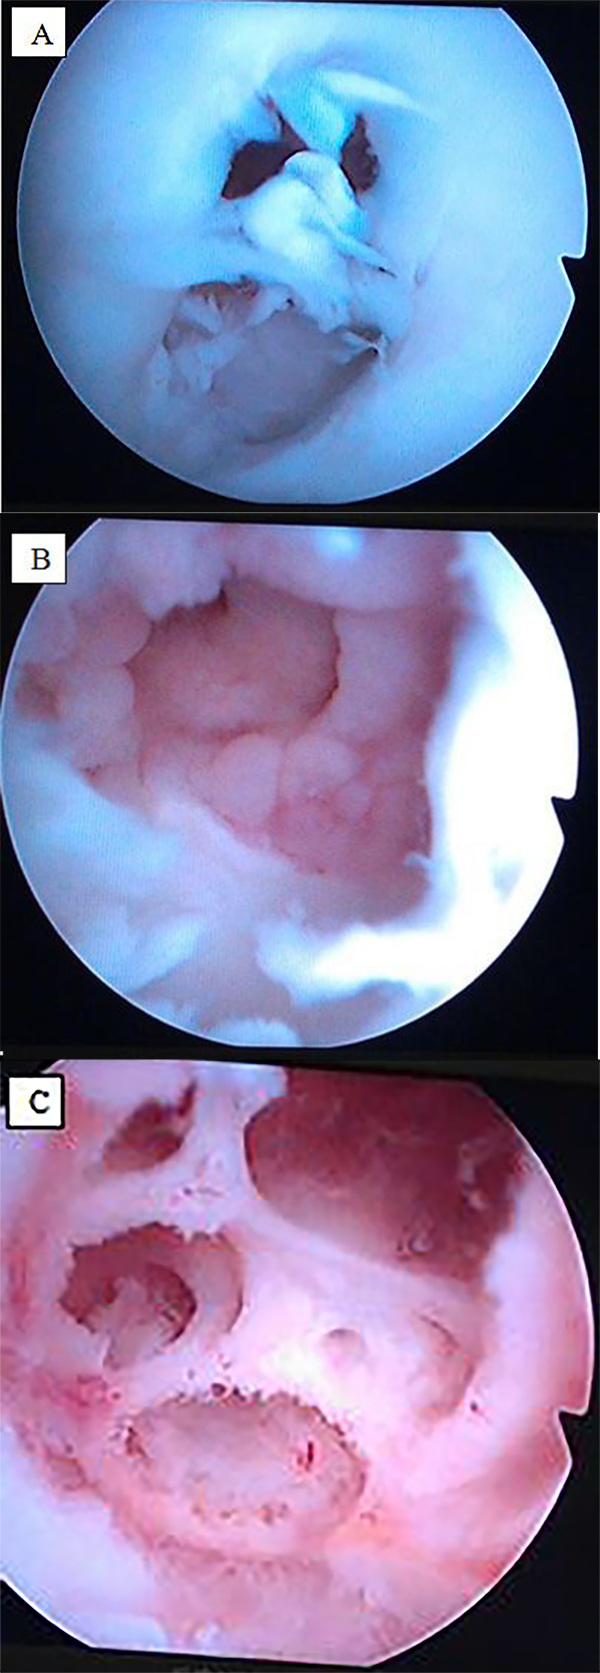

Ante la sospecha de osteomielitis cóndilo femoral externo y artritis séptica de rodilla derecha, se indicó tratamiento quirúrgico. Se realizaron 2 procedimientos artroscópicos: el primero, incluyó lavado-desbridamiento, curetaje del foco, y toma de muestras para estudio microbiológico y anatomopatológico y un segundo dos días después para revisión y nuevo lavado. La artroscopia confirmó la lesión osteocondral con un defecto óseo cavitado de más de 1,5 cm de profundidad y pérdida del cartílago articular (fig. 2A, 2B, 2C).

Figura 2: A) Primera visión artroscópica del cartílago articular del cóndilo femoral externo severamente dañado. B) Visión tras desbridamiento artroscópico y curetaje del defecto cavitario óseo en cóndilo femoral externo. C) Visión en profundidad del foco de osteomielitis tras desbridamiento.